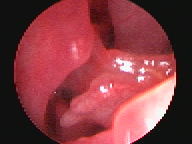

Endoscopia Rígida

A Clínica Veterinária de Albufeira já disponibiliza serviços de minima invasão como solução alternativa às cirurgias tradicionais, sejam estas profiláticas (como as ovariohisterectomias, orquiectomia de criptorquideos) ou de diagnóstico (biópsia, cistotomias, etc). A mais valia desta técnica é a utilização de orifícios naturais ou incisões minímas para aceder ao sistema desejado ( urinário, respiratório, digestivo, reprodutivo), sendo a recuperação mais rápida e a dor pós operatória muito menor.